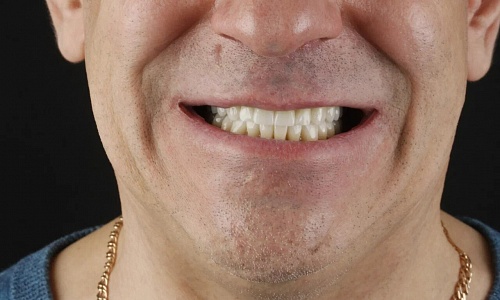

до

после

Отбеливание зубов ZOOM-4

Гигиенист, специалист по отбеливанию зубов на Ленина, 12